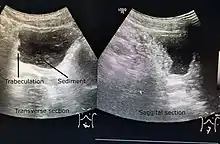

Ultrasound imaging can give information on the shape of the bladder, post-void residual volume, and evidence of kidney damage such as kidney size, thickness or ureteral dilation.[9] Trabeculated bladder on ultrasound indicates high risk of developing urinary tract abnormalities such as hydronephrosis and stones.[10] A voiding cystourethrography study uses contrast dye to obtain images of the bladder both when it is full and after urination which can show changes in bladder shape consistent with neurogenic bladder.[9]